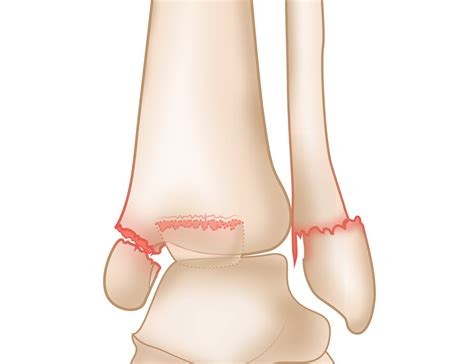

The medial malleolus is a bony protrusion on the inner side of the ankle, part of the tibia bone. It plays a critical role in stabilizing the ankle joint and providing support during movement. The medial malleolus, along with the lateral malleolus (part of the fibula) and the posterior malleolus (part of the tibia), forms the ankle mortise, which helps to hold the talus bone in place. A fracture in this area can significantly impact the stability and function of the ankle.

For more severe fractures, surgery may be necessary to realign the bones and stabilize the joint. Surgical options include:

• Open Reduction and Internal Fixation (ORIF): Involves making an incision to realign the bones and using plates, screws, or rods to hold them in place.